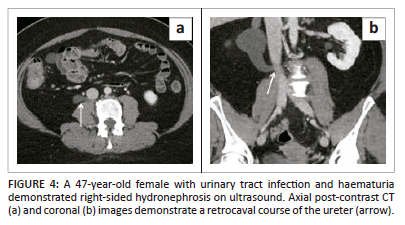

Retrocaval or circumcaval ureter

The genitourinary system develops separately from the IVC. However, embryogenesis of the IVC determines the spatial relationship between the ureter and the IVC. In this anatomical variant, the infrarenal segment develops from the right posterior cardinal vein, which is anterolateral to the ureter, instead of the right supracardinal vein, which is posteromedial to the ureter. The anomaly almost always occurs on the right side with a handful of cases reported on left.9,21 The reported prevalence of a retrocaval ureter is 0.13%.22 In intravenous urography, the proximal part of retrocaval ureter makes a characteristic course. It projects over or medial to the lumbar pedicles. This gives the characteristic fish hook or reverse J appearance (Figure 4).7,9,19 Although most cases are asymptomatic, right flank pain is the most common symptom.21 Compression of the ureter between the IVC and vertebra can result in hydronephrosis. Ureteral obstruction or recurrent urinary tract infection (UTI) may necessitate surgical relocation of the ureter anterior to the cava.9,19,21 Coexistence of other congenital genitourinary, cardiovascular and spine abnormalities have been reported.21